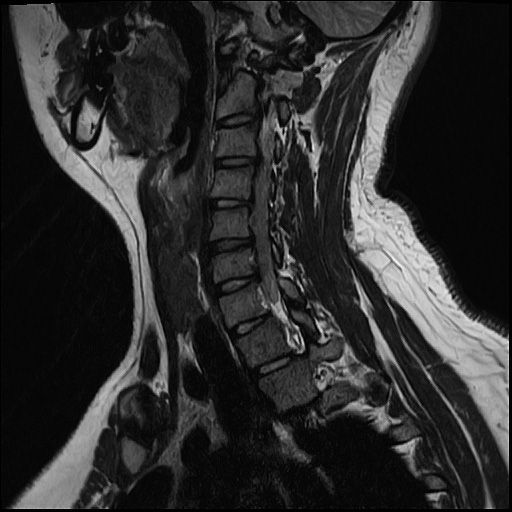

20살 허리디스크 심각한가요?

목디스크 허리디스크 둘다 가지고 있는데 목 몇번이랑 허리 몇번이 터졌고 어느정도 상태인건가요??

올리신 사진들만으로 정확한 디스크 평가가 가능하지는 않습니다. 하지만 사진의 소견들만 보았을 때에는 심하지는 않습니다.

MRI 4컷으로는 디스크 탈출의 정도를 충분히 확인이 불가능합니다.

현재 주어진 사진에서는 허리 디스크는 확인이 가능한 상태이며 그 중등도는 명확히 확인이 어렵습니다.

현재 mri에서는 디스크가 돌출된 부분이 확인됩니다. 디스크가 돌출되었다고 반드시 수술적 치료를 하는 것은 아닙니다. 디스크는 재흡수 되는 경우도 많기에 보존적 치료를 하면서 경과를 보실수 있습니다. 다만 증상이 너무 심하거나 보존적 치료에도 호전이 되지 않는다면 시술이나 수술적 치료를 고려할수 있습니다.